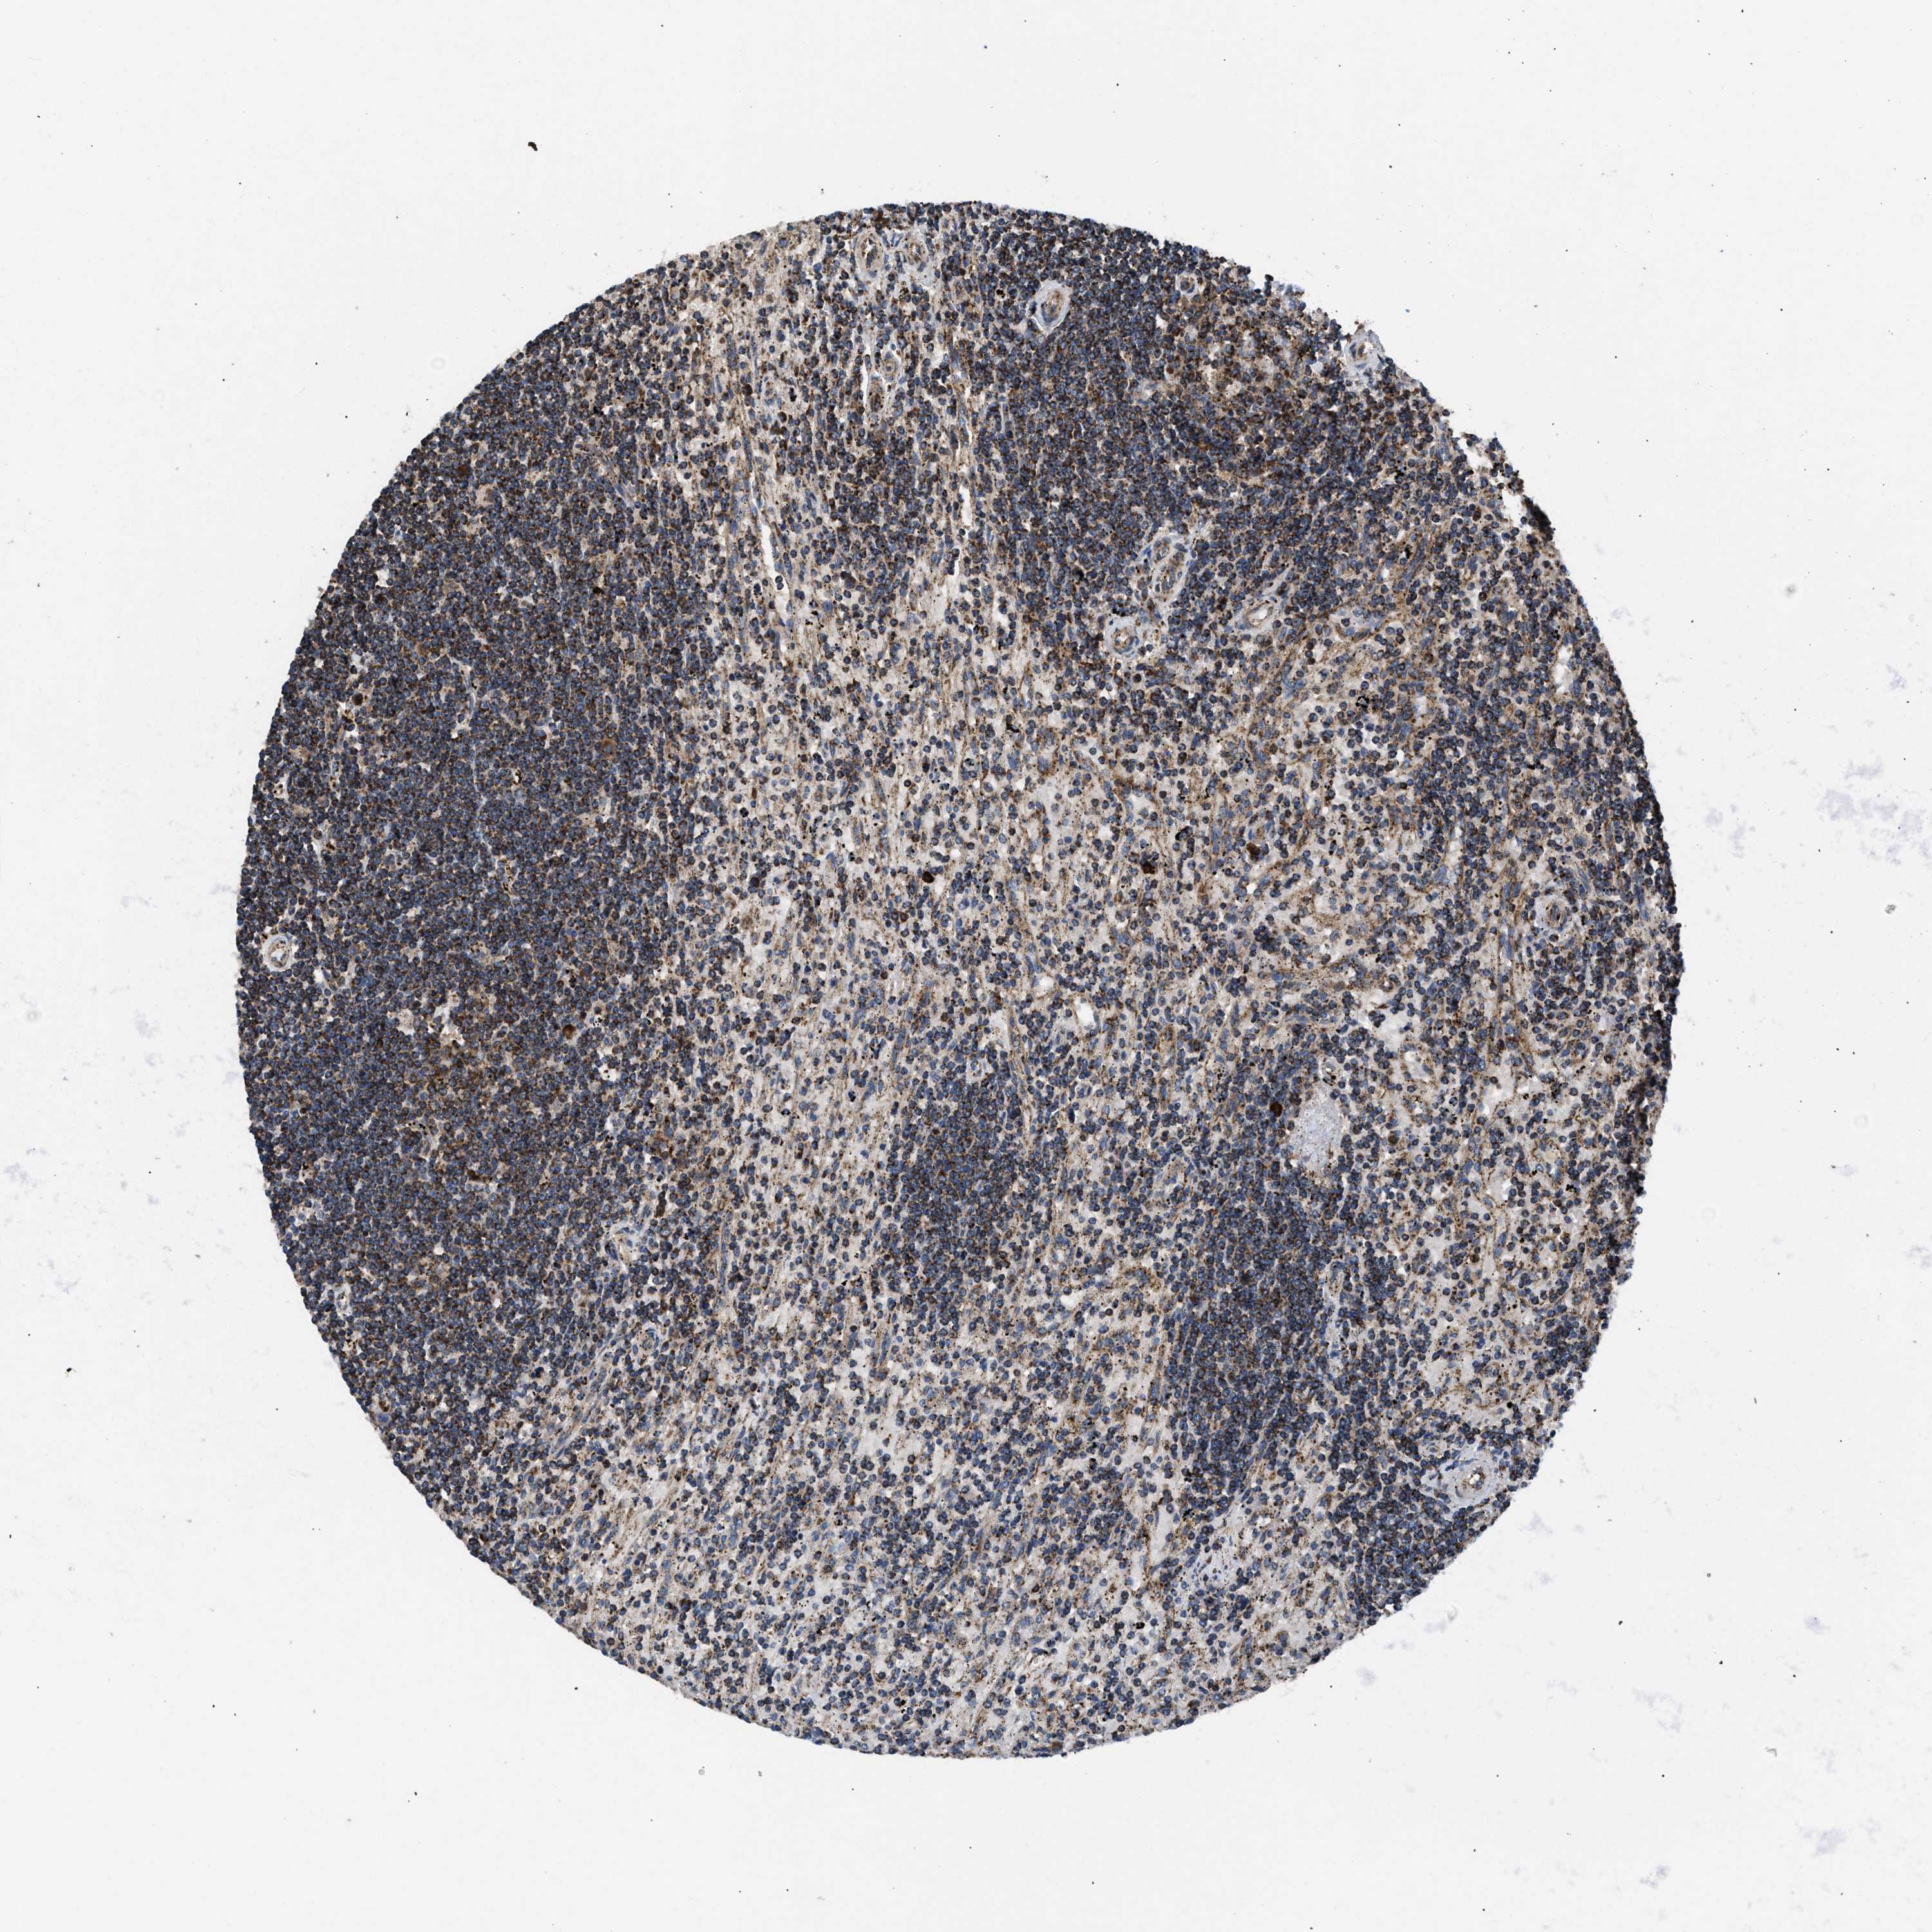

CANCER LYMPHOMA Show tissue menu

LYMPHOMA - Protein expressioni

A mouse-over function shows sample information and annotation data. Click on an image to view it in a full screen mode. Samples can be filtered based on level of antibody staining by selecting one or several of the following categories: high, medium, low and not detected. The assay and annotation is described here.

Each image is clickable and will lead to virtual microscopy that enables deeper exploration of all samples and also displays staining intensity scores, fraction scores and subcellular localization as well as patient and tissue information for each sample.

Antibody HPA003279

Antibody HPA003360

Antibody CAB019303

Malignant lymphoma, non-Hodgkin's type, High grade

Malignant lymphoma, non-Hodgkin's type, Low grade

Hodgkin's disease, NOS